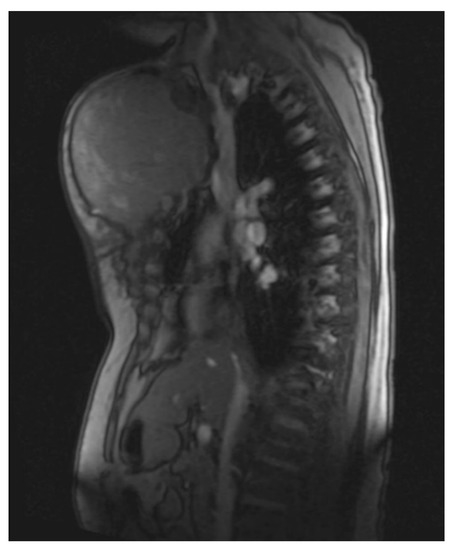

She returned to Bochum in June 2018 with the following symptoms: on the right ventral chest wall, she had a large tumor with a perforation in the pericardium of approximately 15 × 20 cm, an abdominal inguinal tumor on the right, and an ulcerating tumor on the lower left side of the abdomen. A computed tomography of the thorax and abdomen was performed in 09/2018 (Figure 2 and Figure 3) and a magnetic resonance imaging of the thorax was performed in 06/2018 (Figure 4 and Figure 5).

Figure 4.

Magnetic resonance imaging (MRI 2018) showing the large tumorous masses on the anterior thoracic wall, infiltration of the mediastinum per continuitatem, and contact with the aorta.

Figure 5.

Magnetic resonance imaging (MRI 2018) showing the bis soft tissue structure, partially calcified and infiltrating the sternum.